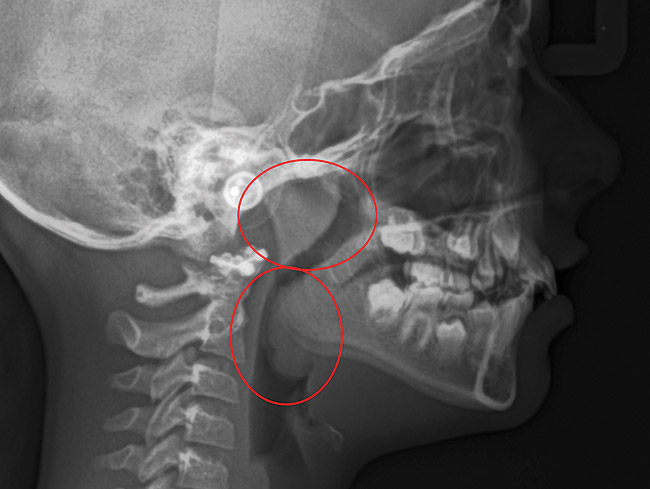

(15.) Cephalometric evaluation demonstrates significant tonsillar blockage of the airway and bimaxillary retursion.

Figure 15